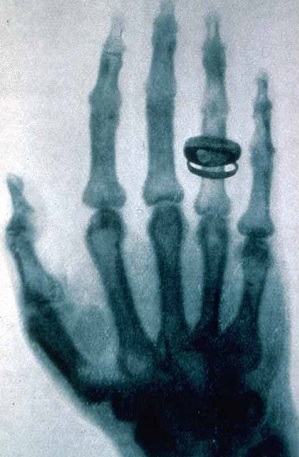

Po 50 d. įtempto darbo Rentgenas pagaliau atskleidė savo paslaptį žmonai Bertai: paprašė ją palaikyti rankos plaštaką ant fotografinės plokštelės. Kai ją išryškino, nustebusi Berta joje išvydo kaulų atvaizdą su vestuviniu žiedu. Netrukus Rentgenas šią nuotrauką pademonstravo Viurcburgo1) fizikų ir medikų draugijos nariams. Jis parengė pranešimą apie naujos rūšies spindulius. Atradimas buvo iškart pripažintas, pranešimas iškart išleistas atskira brošiūra. Tas pranešimas yra pavyzdys, kaip labai svarbų dalyką galima pasakyti labai glaustai  17-a trumpų tezių, išdėstytų tik keliuose puslapiuose. Netrukus brošiūra buvo išversta į anglų, rusų, prancūzų, italų kalbas.